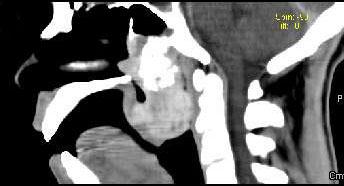

问题 男性,57岁,睡觉打鼾,近来加重,CT扫描如图所示,请选择正确的描述和答案()

选项 A.鼻咽腔偏右侧可见类圆形软组织块影 B.肿块内密度尚均匀,其上方见较多钙化影 C.肿块边缘大部清楚,邻近结构未见明显受侵 D.考虑为鼻咽癌 E.考虑为鼻咽部多形性腺瘤

答案 ABCE